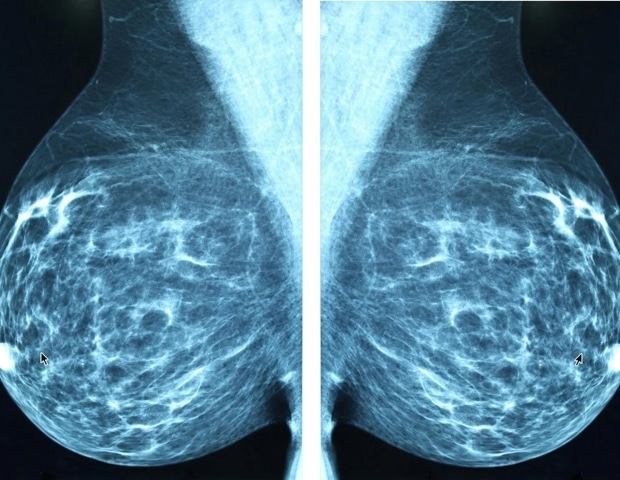

Μια νέα εθνική έρευνα αναδεικνύει ότι πολλές γυναίκες δεν είναι σίγουρες για το πότε θα πρέπει να ξεκινήσουν τις μαστογραφίες, πιστεύοντας ότι η διαδικασία αυτή θα πρέπει να αρχίζει αργότερα από ό,τι προτείνουν οι γιατροί. Συγκεκριμένα, το 44% των γυναικών που συμμετείχαν στην έρευνα νομίζουν ότι οι ετήσιες μαστογραφίες θα πρέπει να ξεκινούν από την ηλικία των 50.

Ωστόσο, οι leading ιατρικοί οργανισμοί προιστάνουν ότι οι γυναίκες με μέσο κίνδυνο για καρκίνο του μαστού θα πρέπει να ξεκινούν τις ετήσιες εξετάσεις από την ηλικία των 40. “Η μεγαλύτερη μας ανησυχία είναι η συνεχιζόμενη σύγχυση σχετικά με τις κατευθυντήριες γραμμές για την εξέταση. Για τις περισσότερες γυναίκες, η μαστογραφία θα πρέπει να αρχίζει ετησίως στα 40,” δηλώνει η Δρ. Alyssa Cubbison, ακτινολόγος του OSUCCC – James.

Η σύγχυση συνέχει ακόμη και μετά την αναθεώρηση των προτάσεων του U.S. Preventive Services Task Force (USPSTF) τον Απρίλιο του 2024, οι οποίες προτείνουν οι γυναίκες με μέσο κίνδυνο να κάνουν μαστογραφία κάθε δύο χρόνια ξεκινώντας από τα 40. Παρ’ όλα αυτά, πολλές ιατρικές ειδικοί, συμπεριλαμβανομένων της Society of Breast Imaging και του American College of Radiology, συνεχίζουν να επιμένουν στη συνιστώμενη ετήσια εξέταση από την ηλικία των 40, ένα πρότυπο που ακολουθεί και το OSUCCC – James.

Παρά την σύγχυση, περισσότερο από το ήμισυ (51%) των γυναικών πιστεύει ότι οι μαστογραφίες θα πρέπει να γίνονται κάθε χρόνο και 41% νομίζουν ότι θα πρέπει να αρχίσουν από τα 35. “Η υποβολή σε μαστογραφία πριν από τα 40 είναι κατάλληλη μόνο για ορισμένους ασθενείς που θεωρούνται υψηλού κινδύνου, λόγω οικογενειακού ιστορικού ή γενετικών μεταλλάξεων,” προσθέτει η Δρ. Cubbison.

Η σύγχυση γύρω από τις κατευθυντήριες οδηγίες προκαλεί ανησυχία, καθώς οι διαγνώσεις καρκίνου του μαστού σε νεότερες γυναίκες αυξάνονται. Το 2022, περισσότερες από 27,000 γυναίκες κάτω των 45 ετών διαγνώστηκαν με καρκίνο του στήθους, με αριθμούς που δείχνουν μέση αύξηση 0.7% ετησίως από το 2001 έως το 2022. Αφού οι νεότερες γυναίκες δεν υποβάλλονται τακτικά σε εξετάσεις, οι καρκίνοι σε αυτή την ομάδα είναι πιο πιθανό να ανακαλυφθούν σε προχωρημένο στάδιο.